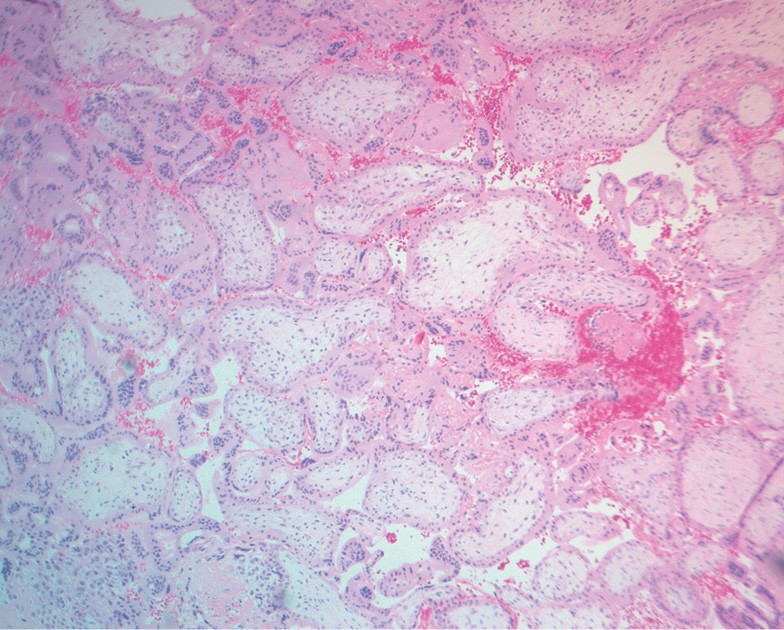

两组均以螺旋动脉壁玻璃样变(68.27–69.23%) 为特征。淋巴细胞和巨噬细胞浸润在单倍体组中多为中度(51.92%),25%的病例为轻度(表2)。各种染色体绒毛膜异常组的淋巴细胞和巨噬细胞浸润明显增多(30.18%有强度浸润,67.46%有中度浸润)(见表2)。此外,染色体异常者明显更有可能在蜕膜组织中出现微脓肿和坏死变化(图2)。

图2 染色体绒毛膜异常的蜕膜组织(微脓肿)苏木精-伊红染色,增大×100倍

染色体绒毛膜异常组的子宫内膜在大多数情况下(88.13%)也有中度至重度淋巴细胞和巨噬细胞浸润的特征(表3)。与整倍体组相比,微脓肿型白细胞聚集的频率几乎增加了3倍(p<0.001)(图3)。 正常核型组的特点是缺乏蜕膜转化约三分之一的病例,有轻度至中度的炎症浸润(见表3)。